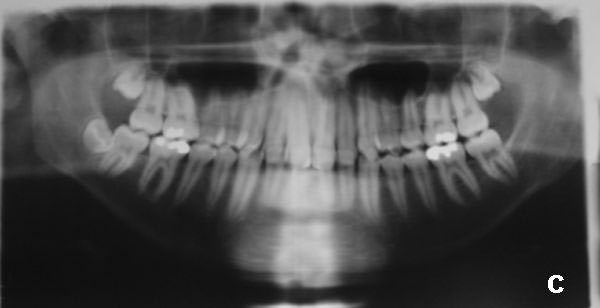

Figura 5

(A) Radiografía Carpal, mostrando que el paciente se encuentra pasando el pico de crecimiento puberal.

(B) Radiografía panorámica en T1 (tiempo 1).

(C) Telerradiografía en norma lateral T1.